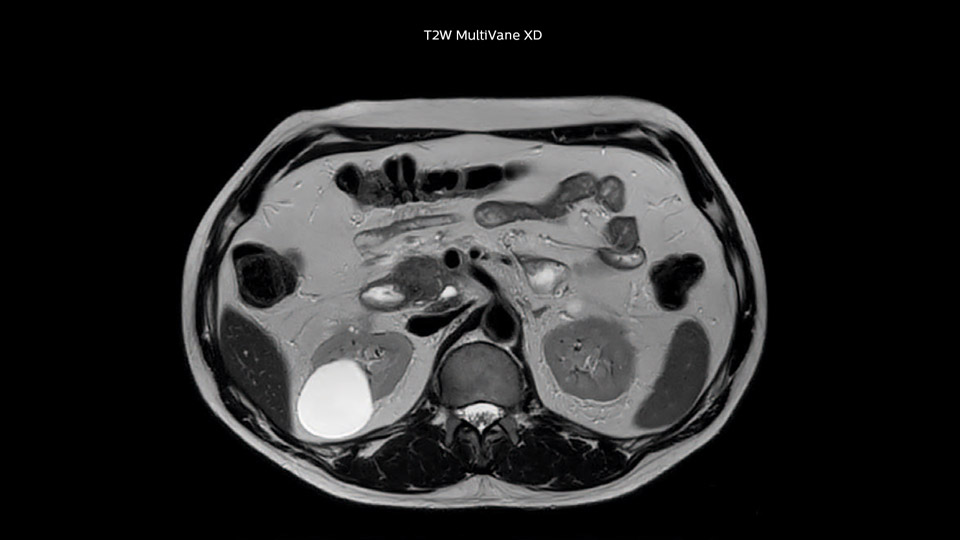

“We acquire one transversal high resolution T2-weighted sequence with 3 mm slice thickness, for example for pancreas or liver lesions. Then we also add a T2 fat suppressed MultiVane XD SPIR sequence. We perform these two routinely in our liver imaging. We use high dS SENSE factors to significantly shorten scan times to 2-4 minutes, which can improve our protocol; it’s a very robust scan.”

“We include mDIXON for the dynamic sequences because of the robust and homogeneous fat suppression we get with that. We had been using eTHRIVE, but we are now quite happy with mDIXON. Sometimes we use a medication to calm the bowels, to further improve the image quality.”